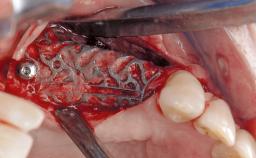

In this case, Myroslav Solonko, Ignacio Sanz Sánchez and Mariano Sanz present a treatment that aims to eliminate exposed implant threads by modifying the implant surface, converting a moderately-rough surface into a smooth surface.